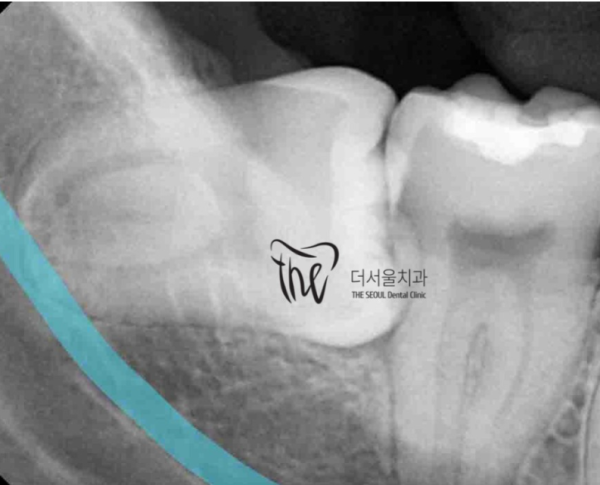

보이시는 것 처럼 이 환자분은 누워있는 사랑니를 발치하고 싶으시다고

하시며 저희 성남치과 더서울치과를 찾아주셨습니다.

As you can see, this patient wants to remove his lying wisdom tooth.

He visited Seongnam Dental Clinic and The Seoul Dental Clinic.

이렇게 누워있는 사랑니는 발치를 하는것이 매우 어렵고

신경써야 하는 부분이 많기 때문에 엑스레이촬영을 자세히 하여

신경관과 뿌리의 거리를 확인하고 발치계획을 세우게 됩니다.

It's very difficult to get a wisdom tooth out lying down like this.

There are a lot of things I need to pay attention to, so I'll take an X-ray in detail.

You check the distance between the neural tube and the root and make an extraction plan.